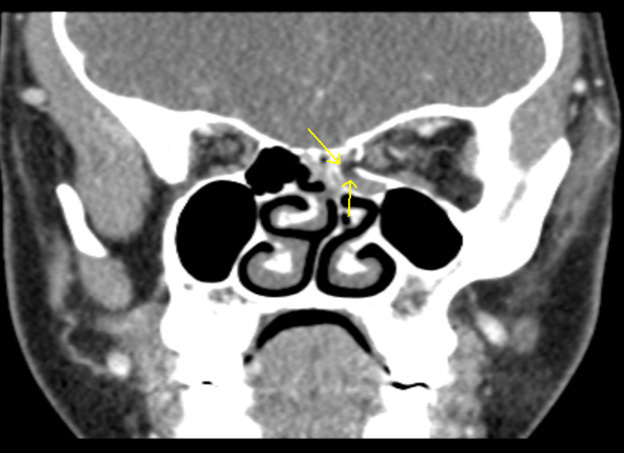

Figure 4 shows an example of a coronal view of a medial orbital wall fracture in a pediatric patient. The image represents a comminuted fracture of the medial orbital wall/lamina papyracea with herniated intra-orbital fat and distortion of the normal morphology of the medial rectus muscle.

Figure 4. Medial Orbital Wall Fracture |

The image shows a comminuted fracture of the medial orbital wall/lamina papyracea with herniated intra-orbital fat and distortion of the normal morphology of the medial rectus muscle. Image courtesy of Mantosh S. Rattan, MD, Radiologist, Orlando Health Arnold Palmer Children’s Hospital, Orlando, FL. |